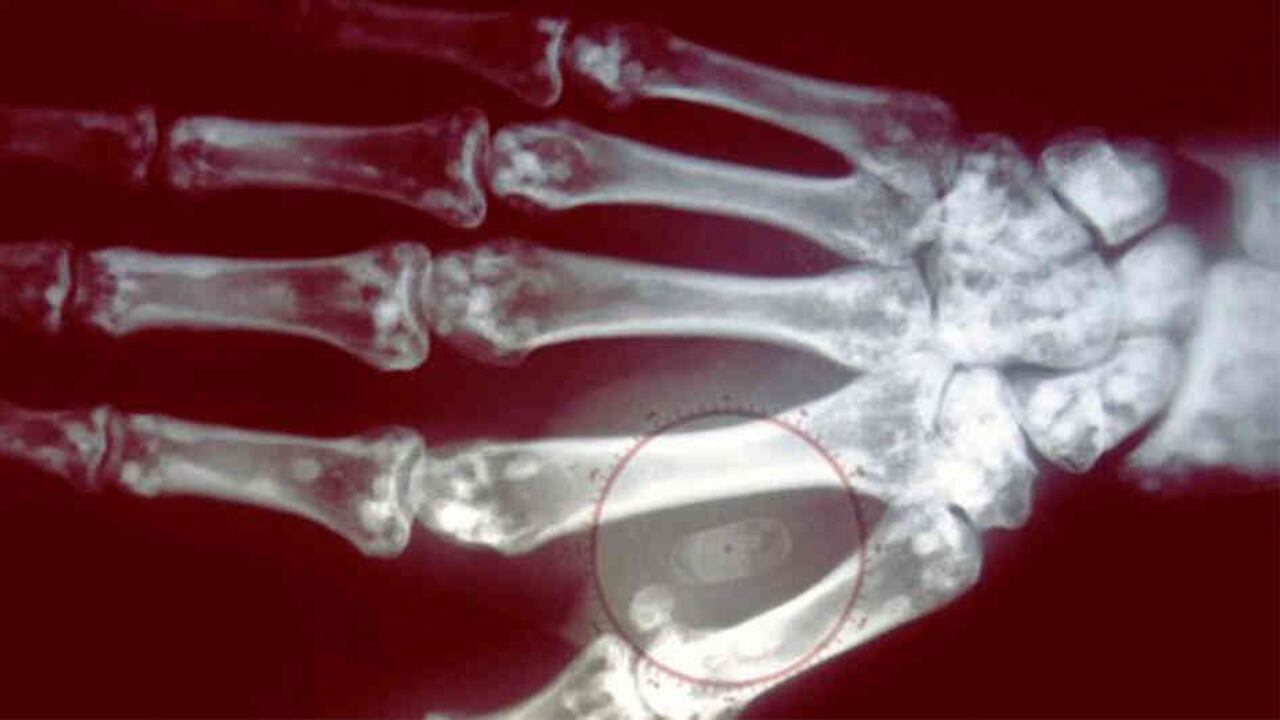

Image captionLos microchips tienen el tamaño de un grano de arroz.

Image captionEl microchip se coloca debajo de la piel, entre los dedos índice y pulgar.